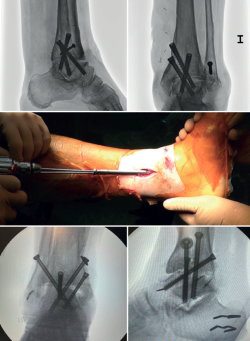

In arthroscopic ankle arthrodesis, the use of percutaneously placed compression screws is the technique of choice (Figure 5).

Most authors consider the use of cannulated screws (3 to 4) to be the ideal fixation method. The diameters of the chosen screws should be between 6 and 7 mm. This technique achieves 85-100% fusion and 84-95% patient satisfaction rates(19).

Van Dijk, Kerkhoffs et al.(20) reported excellent results with the use of three screws as the standardized method for ankle arthrodesis.

Screw configuration and placement

Depending on the deformity involved and according to preoperative planning, screw placement is carried out starting with the compression screw that counteracts the deformity.

In other words, in arthropathies with a varus component, we would start with a lateral screw, while in valgus misalignments the recommendation is to place the first screw from the medial side. The second screw should be on the side opposite to the first. Both should provide adequate compression between the joint surfaces(17).

In general, a minimum of three screws are used. The third screw is the so-called home run screw, the importance of which has been highlighted by Holt et al.(21). It is directed across the ankle from the posterior part of the tibia to the neck of the talus. A fourth screw may be used as an augmentation of the first, counteracting the main deformity.

Goetzmann et al.(22), in their review of 111 cases, supported the use of at least three screws for fixation of arthroscopic tibiotalar arthrodesis. The addition of a third screw appears to be associated with a lower risk of pseudarthrosis and shorter consolidation time. These effects can be attributed to an increased stability of the construct.

Glick, Myerson(23) et al. reported that the configuration conferring the greatest rigidity to the osteosynthesis comprises two screws from medial and one from the lateral side.